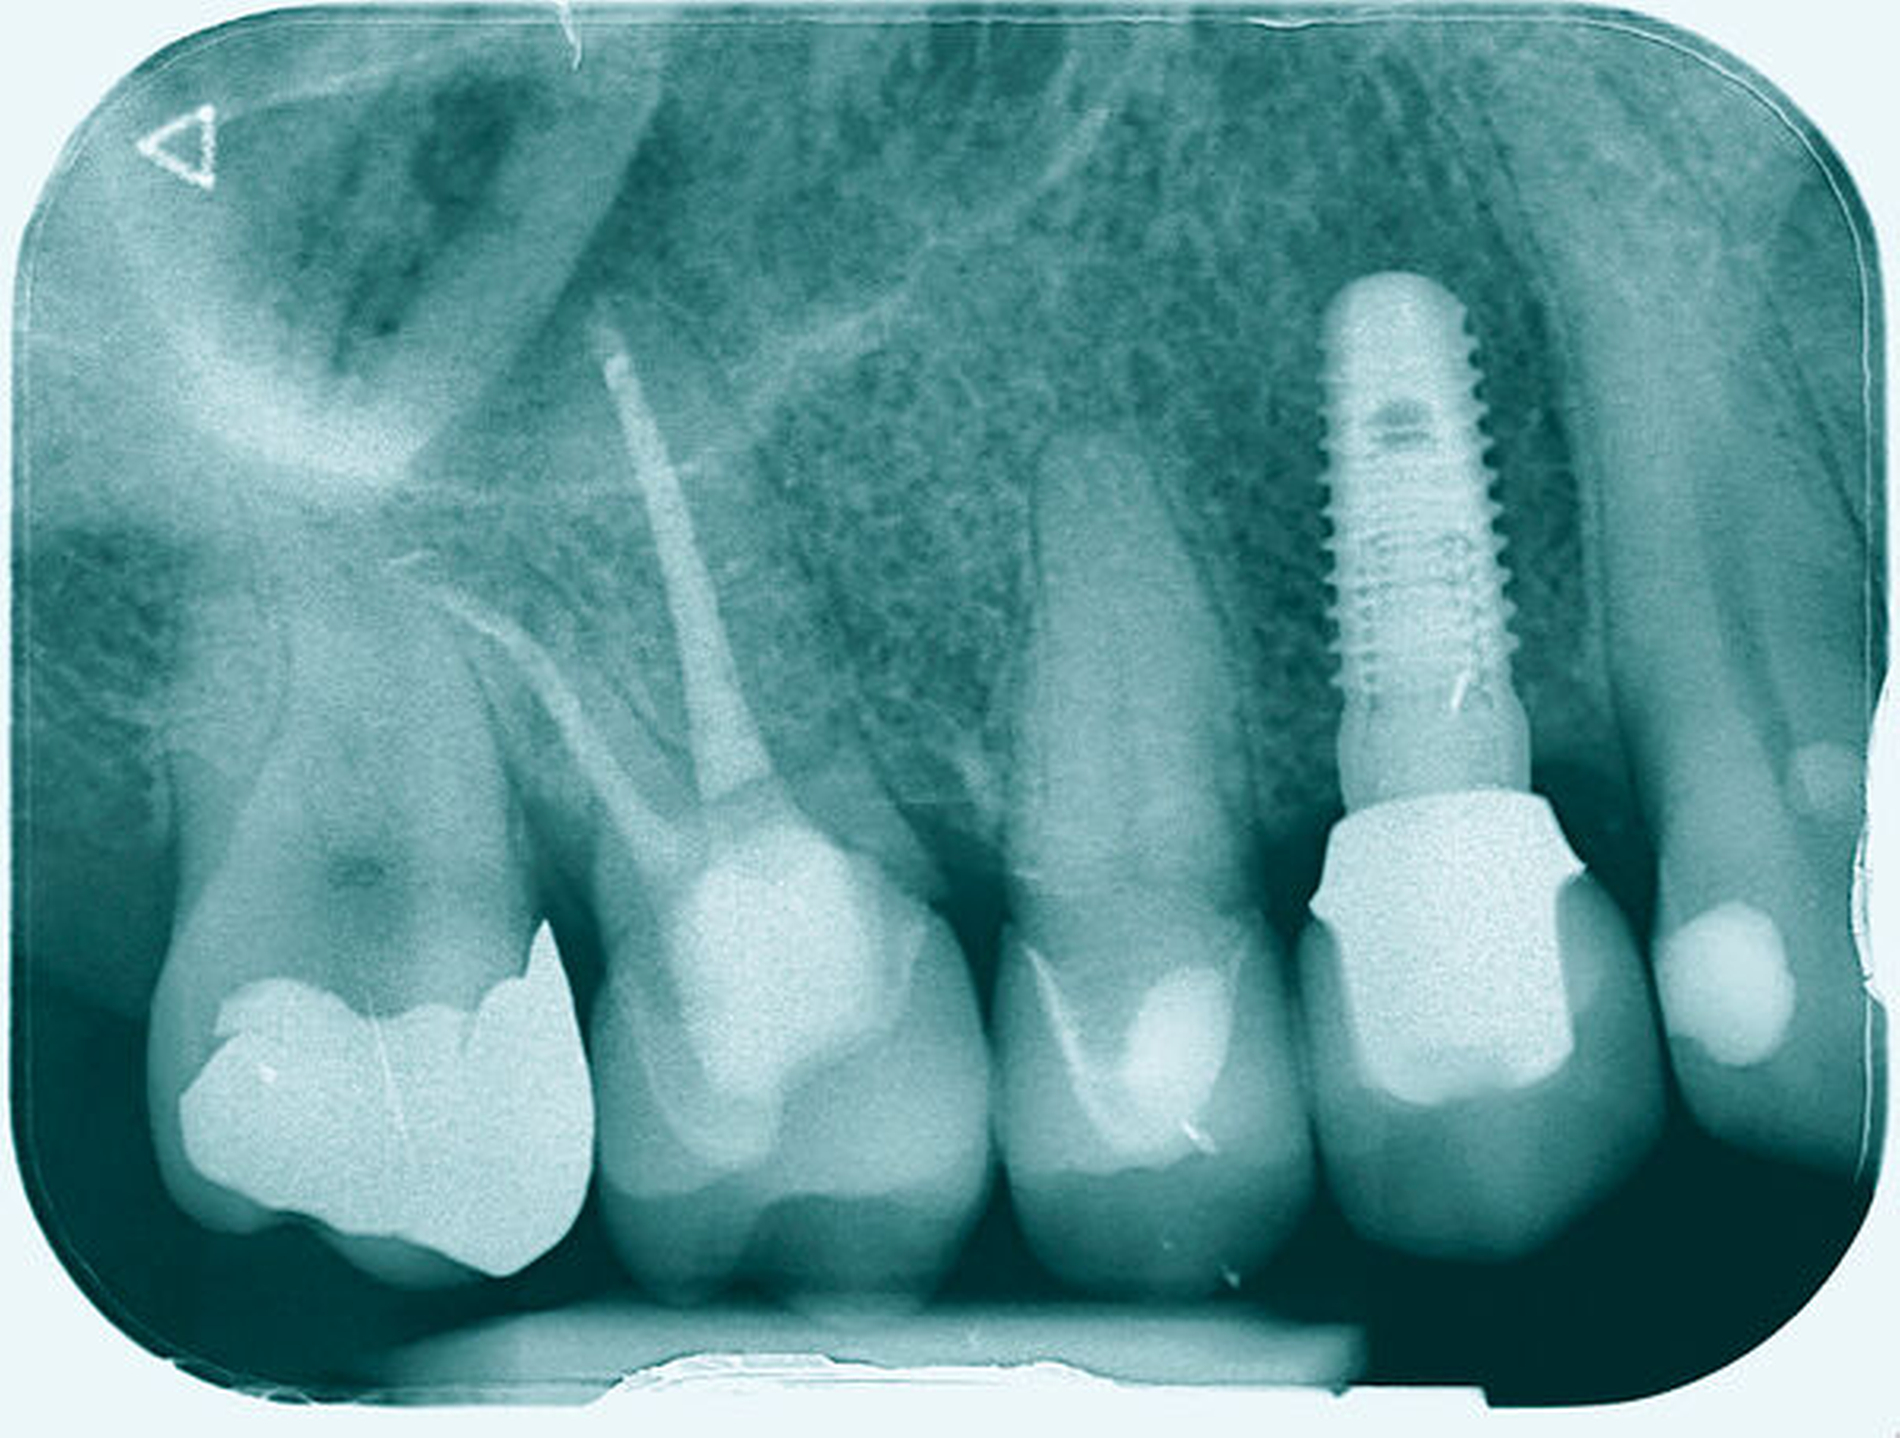

Im Rahmen der Versorgung erfolgte auch ein Austausch der Extensionsbrücke 16–14 durch Einzelkronen auf 16 und 15 sowie einer Implantatversorgung mit Einzelkrone in Regio 014. Der Erhalt des Zahnes 16 ermöglichte so eine wenig invasive Versorgung des ersten Quadranten mit guter Hygienefähigkeit. Alternativ wäre bei Extraktion des Zahnes die Versorgung beispielsweise mit einer ausgedehnten Brückenkonstruktion von 13–17 oder einem weiteren Implantat in Regio 016, vermutlich mit (indirektem) Sinuslift, notwendig gewesen. So konnte der Fall minimalinvasiv zufriedenstellend gelöst werden. Die Patientin ist seit dem Eingriff beschwerdefrei und kommt gut zurecht. Die Situation ist nun seit sechs Jahren stabil.

Eine 46-jährige Patientin klagte 2014 über wiederkehrende Beschwerden an Zahn 16, die sich auch nach einer endodontischen Behandlung nicht besserten. Wiederholt waren submuköse Abszesse aufgetreten. Lokalisiert war die Sondierungstiefe stark erhöht, was auf eine Längsfraktur der mesiobukkalen Wurzel hindeutete. Die Patientin wurde über die Möglichkeiten der Amputation der mesiobukkalen Wurzel sowie alternativ der Extraktion des Zahnes aufgeklärt und entschied sich für den Versuch des Zahnerhalts mittels Teilamputation der mesiobukkalen Wurzel.